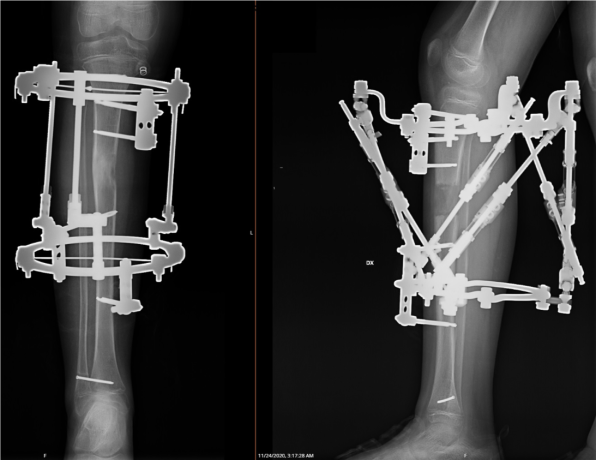

- Ekstremitāšu rekosntruktīvā ortopēdija nozīmē operāciju un tai sekojošu operētās zonas korekciju ar ārējās fiksācijas aparāta, t.s. ortopēdiskā heksapoda palīdzību. Operācija noris, izmantojot spinālo vai vispārējo anestēziju, un ilgst līdz 2 stundām. Pacientam klīnikā jāuzturas vienu diennakti.

- Operācijas laikā tiek veikta osteotomija (kontrolēts lūzums) un uzstādīts ortopēdiskais heksapods – ārējās fiksācijas aparāts, ar kura palīdzību iespējams veikt gandrīz jebkuras deformācijas precīzu korekciju.

- Pēc deformācijas korekcijas pacientam tiek noņemta lielā ortopēdiskā heksapoda konstrukcija - ap koriģējamo ekstremitāti paliek tikai 2-3 fiksācijas gredzeni, kuri neierobežo pacienta mobilitāti.

Ekstremitāšu rekonstruktīvā ortopēdija notiek ķirurģiski ar ārējās fiksācijas - t.s. ortopēdiskā heksapoda palīdzību.